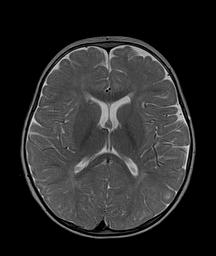

La RMN encefalo di controllo, ripetuta dopo sette mesi, evidenzi� un nettissimo e perfino insperato miglioramento (Figura 2). Attualmente, a 30 mesi: crescita, appetito, umore, relazione e esame neurologico sono praticamente normali.

Figura 2. RMN dopo 7 mesi dalla terapia con cobalamina. Non pi� apprezzabile l�ampliamento degli spazi subaracnoidei e ventricolari; sfumata iperintensit� T2 a livello della sostanza bianca periventricolare occipitale bilaterale compatibile in prima ipotesi con aree di lieve ritardo nella maturazione mielinica.